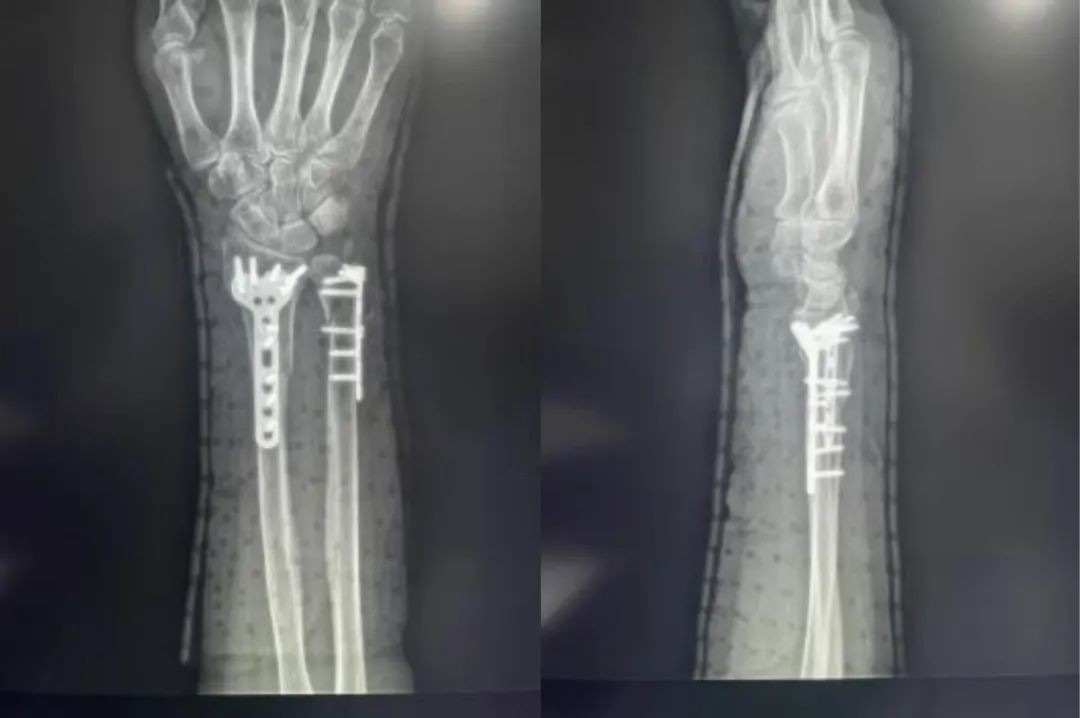

Случай ①